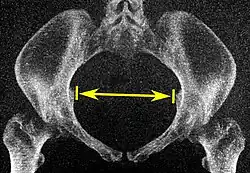

| Pelvic inlet | Transverse diameter of the pelvic inlet |

The iliopectineal lines, at widest transverse distance. | 13 to 14.5 cm.[4] |